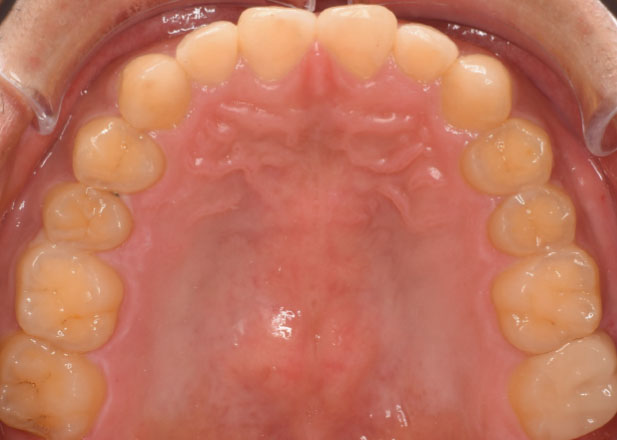

口腔内写真

治療前